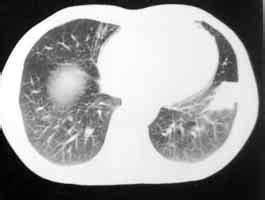

化驗檢查無特殊診斷價值。胸部X線檢查可發現肺部陰影,半數以上的假瘤表現為邊緣光滑、銳利、界限清楚、孤立的圓形或橢圓形結節影。如果假瘤周圍有炎症未吸收,也可表現出邊緣模糊,有“毛刺”。兩個相鄰的假瘤互相融合或生長過程中受到血管的阻擋,可出現“臍凹征”和呈“啞鈴型”。假瘤缺血、壞死,在病灶斷層和CT掃描片上可見空洞。少數有鈣化。腫塊內的小支氣管可保持通暢而表現為“氣道征”。纖維支氣管鏡檢查和經皮肺穿刺活檢有助於鑑別診斷。